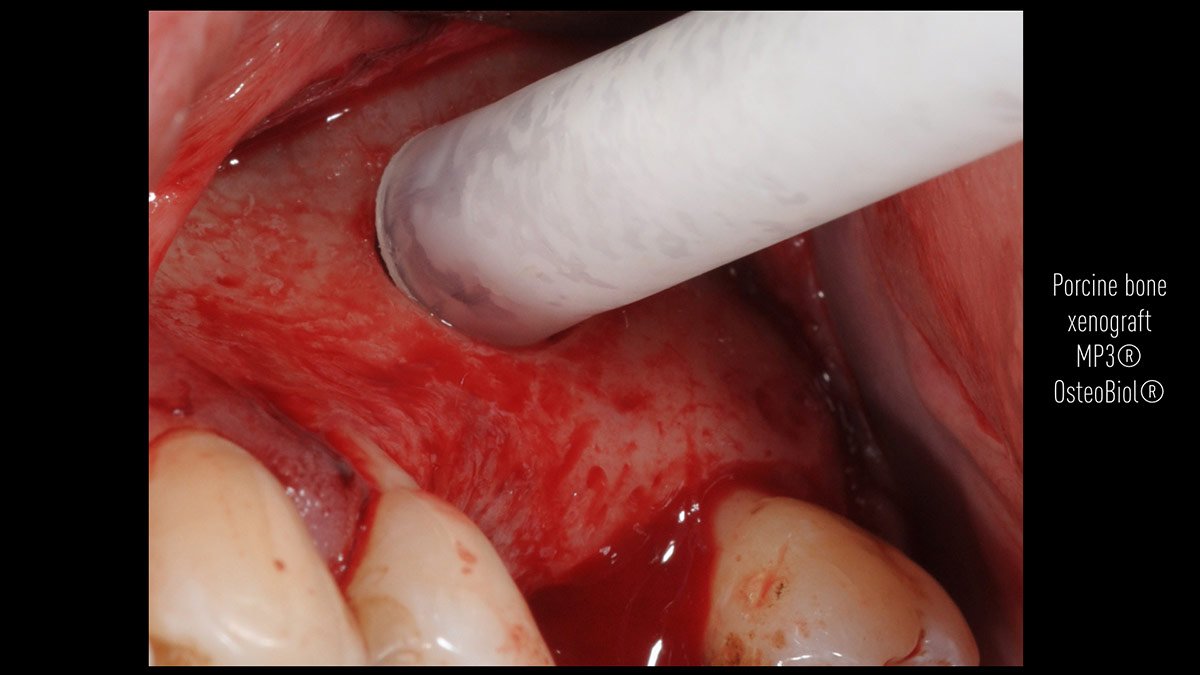

Delayed implant placement; sinus floor elevation by means of lateral approach and implant placement with GBR. Case report by Irfan Abas, M.Sc.